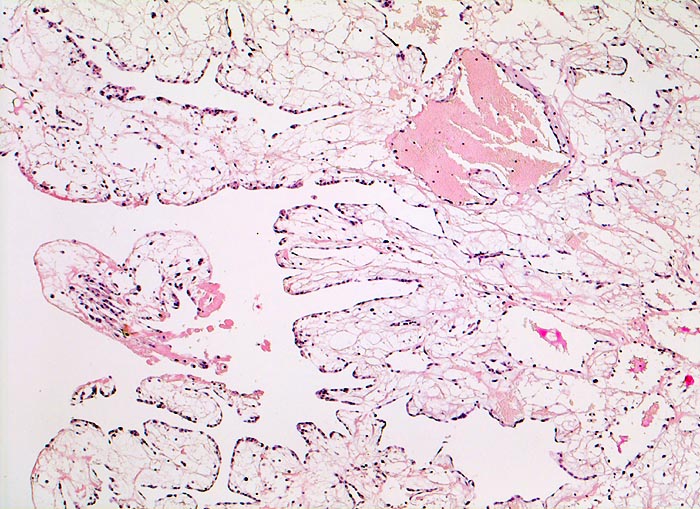

AP/ Vorhofmyxom

Vorhofmyxom

Befund

Pathologischer Befund